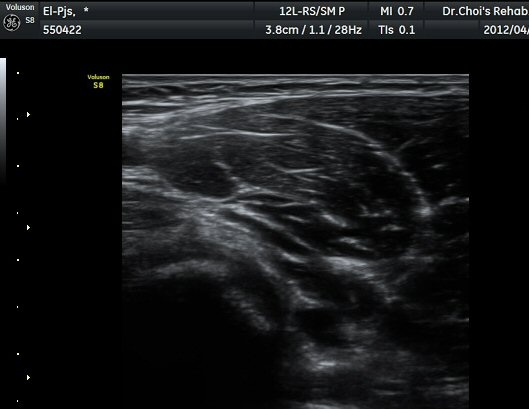

ÆÈ²ÞÄ¡ ¾ÕÂÊ È²µò¸é°Ë»ç¿¡¼­ Á¤»óÀûÀ¸·Î À̵ιڱ٠ÈûÁÙ°ú »ó¿Ïµ¿¸ÆÀÌ °üÂûµÈ´Ù(±×¸² 1).

ŽÃËÀÚ¸¦ ÆÈ²ÞÄ¡ ¸»´ÜÀ¸·Î À̵¿ÇÏ´Ï À̵ιڱ٠ÈûÁÙÀÇ ºñÈÄ¿Í ÈûÁÙ ÁÖÀ§¿¡ Àú¿¡ÄÚ ¼ö¾×Àú·ù°¡ ]

°üÂûµÈ´Ù(±×¸² 2, 3, 4, 5). ŽÃËÀÚ¸¦ ¸»´ÜÀ¸·Î À̵¿ÇÒ ¶§ ŽÃËÀÚ¸¦ ¸Ó¸®ÂÊÀ¸·Î °æ»ç(tilting)½ÃÄѾß

À̵ιڱ٠ÈûÁÙ¿¡ Á÷°¢ ÀÇ ÃÊÀ½ÆÄ Á¶»ç°¡ °¡´ÉÇÏ¿© À̵ιڱ٠ÈûÁÙÀÌ °í¿¡ÄÚ·Î °üÂûµÈ´Ù.